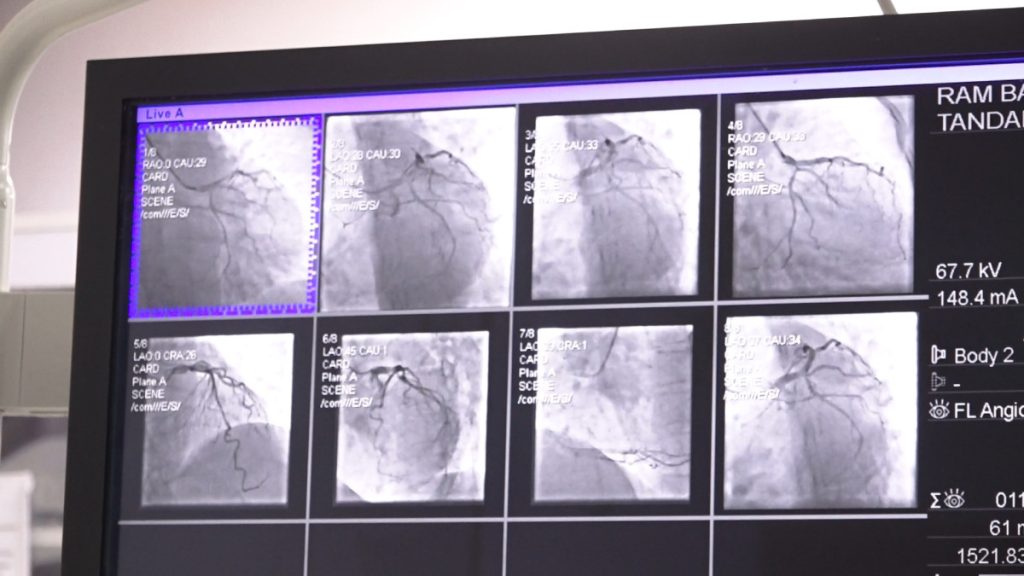

प्रा. ढुङ्गानाका अनुसार क्याथ ल्याव एक विशेष प्रकारको अत्याधुनिक एक्स–रे मेसिन हो । जसले धड्किरहेको मुटु र नशागत समस्याहरूको जाँच तथा उपचार गर्न सकिन्छ । डा. ढुङ्गानाले क्याथ ल्यावमा हृदयको नशा परीक्षणका लागि हात वा खुट्टाको नशामा सानो सुई (सामान्यतः स्थानीय एनस्थेसिया) मार्फत पाइप (क्याथेटर) प्रवेश गराइने बताए । यो प्रविधिमार्फत हृदयका विभिन्न रोगहरू—जस्तै नशा ब्लकेज, जन्मजात मुटुका प्वाल, भल्बको साँघुरो वा अन्य हृदयसम्बन्धी जटिलताहरूको छिटो र सुरक्षित उपचार सम्भव भएको प्रा. ढुङ्गानाले बताए । यस प्रक्रियाले धेरै जटिल रोगहरूलाई सहज र सुरक्षित बनाएको उनले जिकिर गरे ।

उनले भने, ‘यो मेसिन चाहीँ एक विशेष किसिमको एक्स—रे हो । जसरी एक्स—रे मा फोटो खिचिन्छ नि छातीको । सामान्य बुझाइमा भन्दाखेरि छातीको एक्स—रे लिँदाखेरि फोटो खिचिन्छ त्यस्तै यसले चाहीँ के गर्छ भन्दा लाइभ त्यहाँ सुताउने बित्तिकै हामीले पूरा शरीरदेखि गोडा सम्मको अंग हेर्न मिल्छ । यसमा चाहीँ के हुन्छ भने हातको नशा, यो नाडीको नशामा हामीले एउटा लाटो पार्ने सुई दिन्छौं । कहीँ चिरफार हुँदैन एउटा सुई मात्र लाग्छ । त्यहाँ एउटा सामान्य किसिमको पाइप पस्छ । त्यो पाइपको थ्रु चाहीँ हामीले नशा चाहीँ के हुन्छ भन्दा यहाँको हातको र गोडाको नशा चाहीँ मुटुसँग कनेक्ट भएको हुन्छ । त्यो नशाको थ्रु, नशा हुँदै मुटुमा पुगिन्छ ।’

बाइ–प्लेन प्रविधिः दुवै फोटो एकैचोटि

काठमाडौं मेडिकल कलेजले प्रयोग गर्दै आएको क्याथ ल्याव ‘बाइ–प्लेन’ मोडेल भएकाले यस प्रविधिले एकैचोटि दुईवटा फोटो खिच्नसक्ने जसका कारण डाई र विकिरणको मात्रा कम हुने डा. ढुङ्गानाले बताए । उनका अनुसार ‘यसले बिरामीको मिर्गौलामा पर्ने प्रभाव घटाउँछ र चिकित्सकको काम पनि सहज बनाउँछ’ । नेपालमा करिव एक दशक अगाडि भित्रिएको यो प्रविधि काठमाडौं मेडिकल कलेजमा करिव तीन वर्ष देखि उपलब्ध छ । क्याथ ल्यावको प्रयोगले बिरामीलाई डर लाग्ने अवस्था कम हुने, छुट्टि तत्कालै दिन सकिने र महत्वपूर्ण रूपमा समय बचत हुने डा. ढुङ्गाना बताउँछन् ।

उनले भने, ‘काठमाडौं मेडिकल कलेजमा शुरुवात गरेको लगभग तीन, साढे तीन वर्ष भयो र नेपालमा त धेरै वर्षदेखि छ । नेपालमा १०/१५ वर्षदेखि नै यो सेवा विभिन्न सेन्टरहरुमा उपलब्ध छ । तर यो मेसिन चाहीँ हाम्रो अत्याधुनिक टाइपको, हामी बाइ प्लेन भन्छौं, एकैचोटि यसले चाहीँ दुईवटा फोटो खिच्छ । अरु मेसिनमा के हुन्छ भन्दा खेरि हामीले दुई चोटि फोटो खिच्नलाई एउटा डाई हुन्छ त्यो डाइ दिनुपर्ने अनि एक्स—रेको विकिरण बढी लिनुपर्ने हुन्थ्यो भने यसमा चाहीँ एकैचोटी दुईवटा फोटो खिच्ने भएको हुनाले एकैचोटी डाई पठाएर दुईवटा फोटो लिन सकिन्छ । त्यसले अलि सहज पनि हुन्छ । हामी गर्ने मान्छेलाई पनि विकिरणको प्रभाव कम पर्न जान्छ । कतिपय बिरामीको मृगौलामा समस्या आउन सक्ने समस्या सेफ हुन्छ ।’